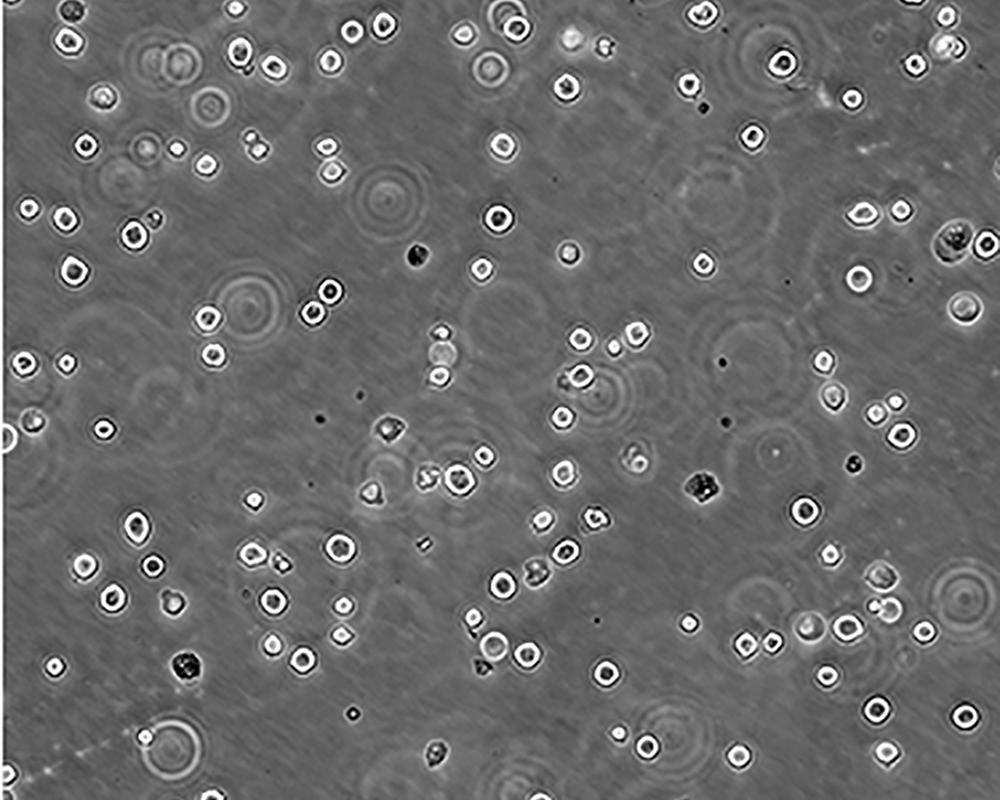

生長特性 suspension

形態(tài)特征 lymphoblast

細(xì)胞描述 The cell population has been characterized as highly undifferentiated and of the granulocytic series. Studies conducted by Anderson, et al. , on the surface membrane properties led to the conclusion that the K-562 was a human erythroleukemia line. K-562 blasts are multipotential, hematopoietic malignant cells that spontaneously differentiate into recognizable progenitors of the erythrocytic, granulocytic and monocytic series. The effect of inducers on sublines derived from the original K-562 cell line have been reviewed by Koeffler and Golde. Karyological studies on various K- 562 sublines have been classified into three groups(A,B,C) by Dimery, et al. The strain obtained by the ATCC most closely resembles the B population. Occurrence of the Philadelphia chromosome, however, was of much lower frequency; none detected in 15 metaphases examined. The line is EBNA negative.